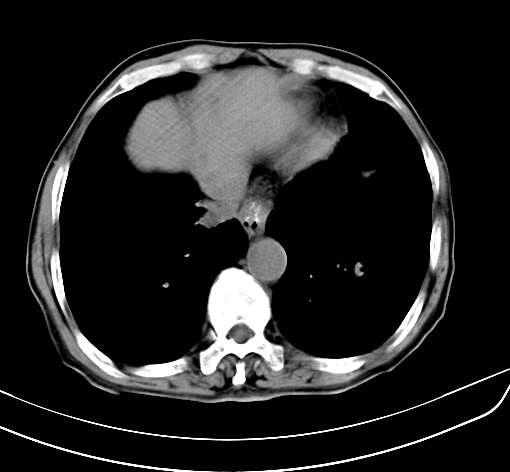

病人 男 70 咳嗽 胃部不适 2月余

1、考虑肝门占位,肝内胆管扩张,建议强化  2胆囊区胆囊显示不佳邻近肝组织内见低密度区是否考虑胆囊癌侵犯肝脏

胆囊壁增厚,与临近肝实质边界不清,临近肝实质内可见大片边界不清之低密度区,肝门区密度亦有减低,部分结构不清,尾叶前方可见块状影,肝右叶可见多枚边界不清之圆形低密度区,肝内胆管扩张征象,结合病史考虑1胆囊癌肝内转移,肝门区淋巴结转移,门脉癌栓待排2肝内胆管扩张3建议增强扫描

肝脏多发大小不等低密度灶,边界不清,肝门区结构不清,肝内胆管轻度扩张,胆囊密度不均匀,内见软组织样密度影,与相临肝脏边界不清.考虑:1、胆囊ca侵犯肝脏并肝内多发转移,肺上也有结节影,转移?建议强化扫描.2、胃充盈不好,如怀疑有病变最好建议做相关检查.

胆囊壁增厚,周围模糊不清,肝内多发低密度影,胃充盈欠佳,胃壁增厚,外形尚规整,考虑胆囊炎、胆囊癌肝内转移?建议胃肠道进一步检查或增强扫描。